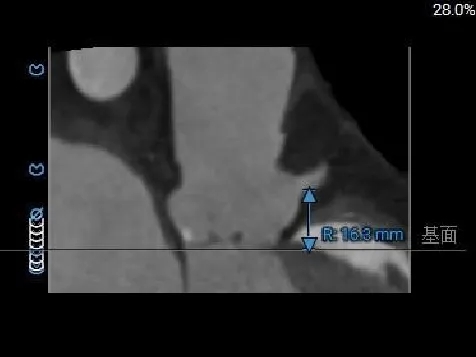

左冠开口高度约为17.6mm,右冠开口高度约为16.3mm,双侧冠脉堵塞风险较低。

冠脉风险评估

LCA Height

RCA Height